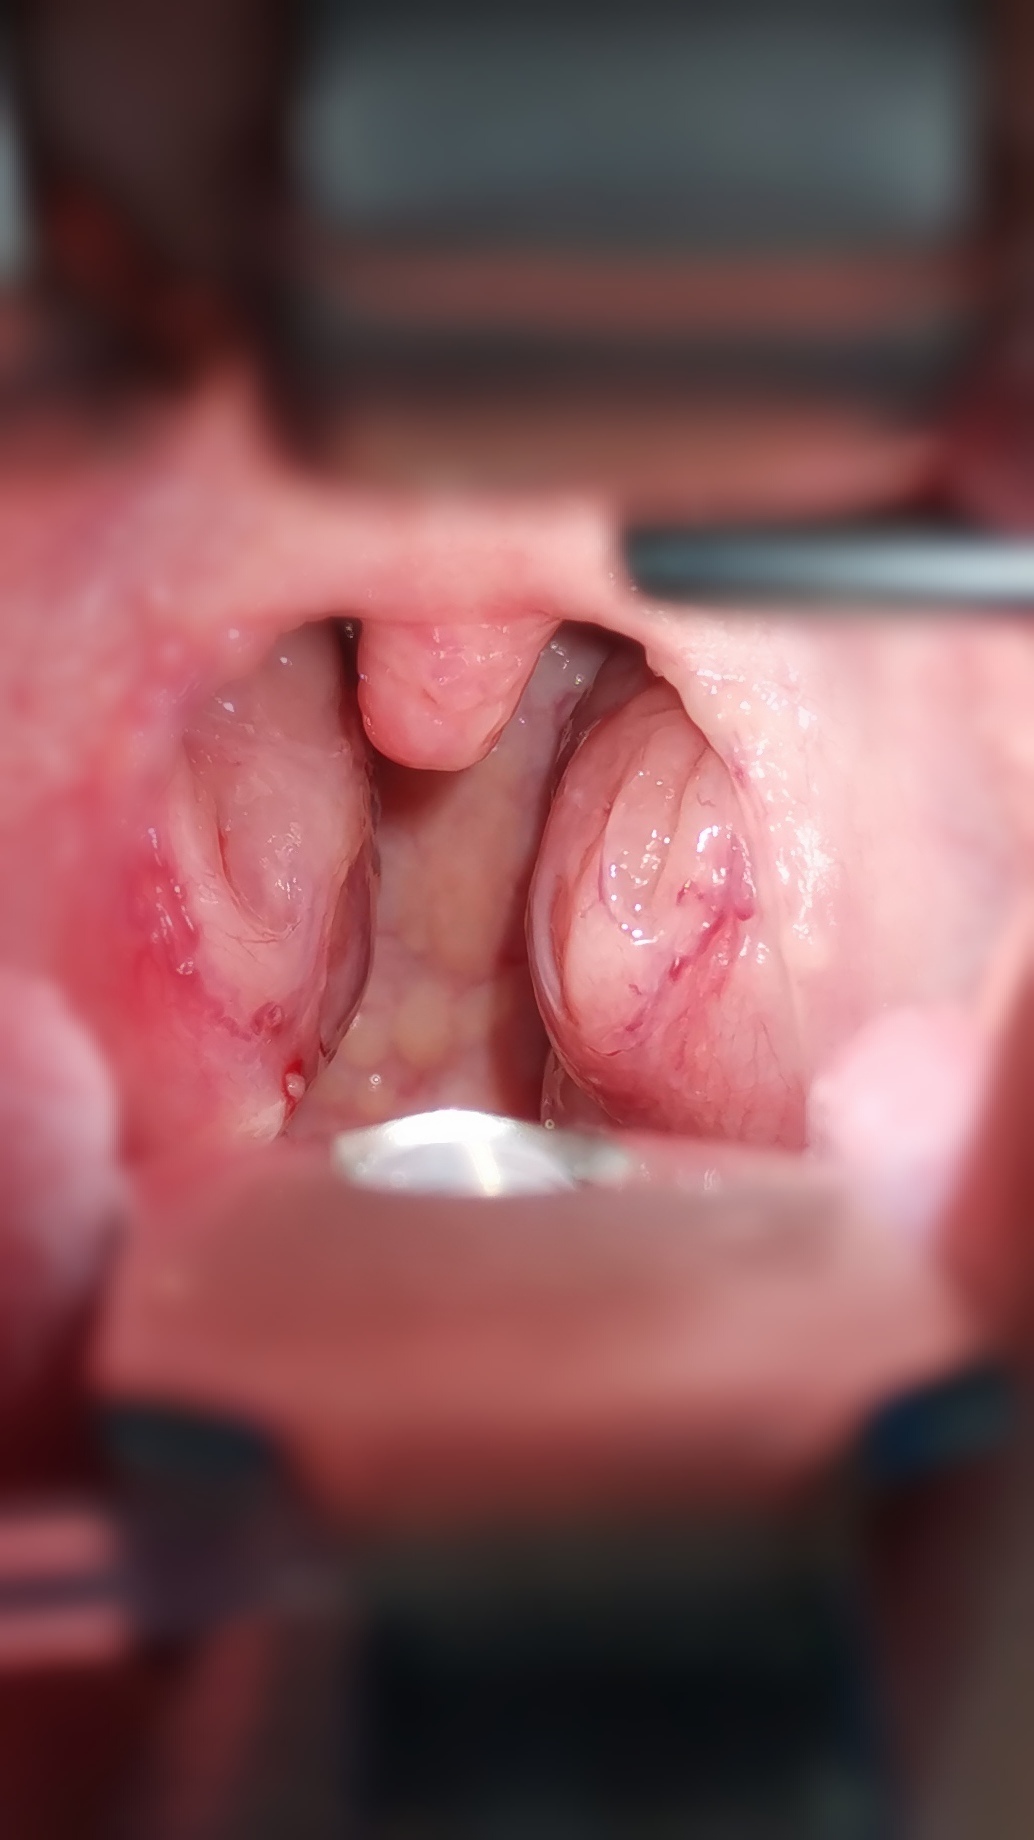

分享一個秘密,醫(yī)生是如何判斷孩子的扁桃體做過灼烙術(shù)

門診就診的時候,有一些家長帶著孩子過來檢查,我看到后就會問孩子扁桃體是不是做過灼烙術(shù)?家長問我是怎么知道的?我給大家分享一下這個秘密!正常肥大的扁桃體,中間段呈弧形外凸,在干嘔的狀態(tài)下,兩側(cè)扁桃體可能會互相擠壓,而做了扁桃體灼烙術(shù)的患兒,雙側(cè)扁桃體的中段弧形凸起消失,會變成凹坑,同時部分孩子還能看到灼烙后的瘢痕。下面是視頻展示,大家可以看一下。